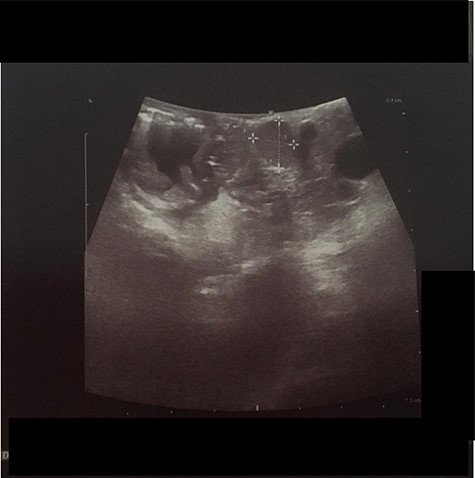

We present the case of 46-year-old female patient suffering from spontaneous hypoglycemia. She was admitted to our hospital due to worsening clinical symptoms. At first, she underwent a 72-hour monitored fast and biochemical testing for endogenous hyperinsulinism, which proved positive. Once the other causes of spontaneous hypoglycemia were excluded, we started the process of localization of insulinoma. Then the patient underwent endoscopic ultrasonography (EUS) of pancreas with the find of hypoechogenic, well demarcated, hypervascular tumor in the head of pancreas size of 12.4 × 10.5 mm (Fig.1). Computed tomography (CT) examination of abdomen followed up and tumor of pancreatic head, corresponding with the diagnosis of insulinoma, was found (Fig. 2). It was located nearby pancreatic and biliary duct. Because of serious clinical symptoms, an early surgical treatment was indicated. Based on the evaluation of the surgeon to perform the less radical surgery, it was suggested to enucleate the tumor with preoperative stenting of pancreatic and biliary duct. Two days before the surgery, ERCP with insertion of pancreatic and duodenobiliary stent was performed (Fig. 3). With regard to the patient's preference and overweight, laparotomic approach was selected. Determination of the exact position of tumor was difficult, insulinoma was hardly palpable. We used intraoperative ultrasonography to identify the exact location of tumor (Fig. 4). Then the surgeon palpated the inserted stents and the insulinoma was identified intrapancreatically, 3–4 mm nearby pancreatic and bile duct. Enucleation of tumor was performed by harmonic scalpel (Fig. 5). During the surgery, the right position of stents was verified by touch. After enucleation, there was no presence of bleeding, the defect was filled with tissue glue (Fig. 6). Macroscopically, tumor was round shaped, well capsulated, size 1 cm (Fig. 7). During postsurgery period, the patient was stable and with no signs of complication. On the sixth postoperative day, endoscopic removal of pancreatic stent was carried out. Patient was discharged from the hospital on the eight postoperative day. Duodenobiliary stent was left in ductus choledochus for 1 month.

IOUS (intraoperative ultrasound) performed during surgery shown hypoechogenic lesion in the head of pancreas (between white marks).